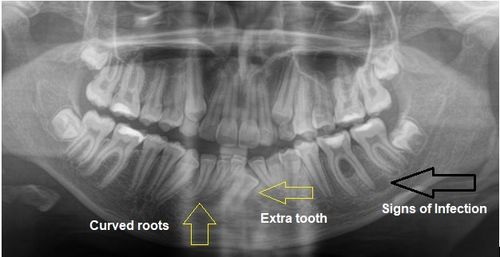

Dental X-rays are an important diagnostic tool that allow us to evaluate areas of the teeth, bone, and supporting structures that cannot be seen during a clinical exam alone. Advances in modern digital radiography have significantly reduced radiation exposure compared to older imaging systems, making today’s dental X-rays both precise and safety-focused.

Digital X-rays provide essential information that supports accurate diagnosis and preventive care, including the ability to assess:

⏺️ Interproximal (between-the-teeth) decay

⏺️ Bone levels and bone health

⏺️ Periodontal diseaseInfections

⏺️ Cysts or tumors

⏺️ Tooth development, eruption patterns, and root positioning, especially in children

Without imaging, many of these conditions may go undetected until they become more complex or symptomatic.

The bitewing X-rays shown below provide an example of how periodontal disease can appear radiographically. X-rays allow us to evaluate bone levels and detect changes or decay that may not be visible during a clinical exam alone, helping guide appropriate and timely treatment.